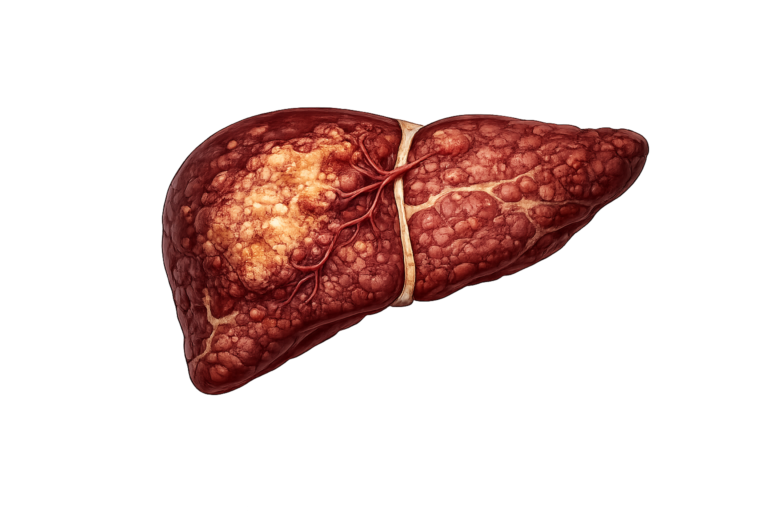

MASH

Fat with inflammation and scarring, i.e. fibrosis

MASH

Fat with inflammation and scarring, i.e. fibrosis

Cirrhosis

Scar tissue replaces the liver cell

Hepatocellular Carcinoma

Irreversible